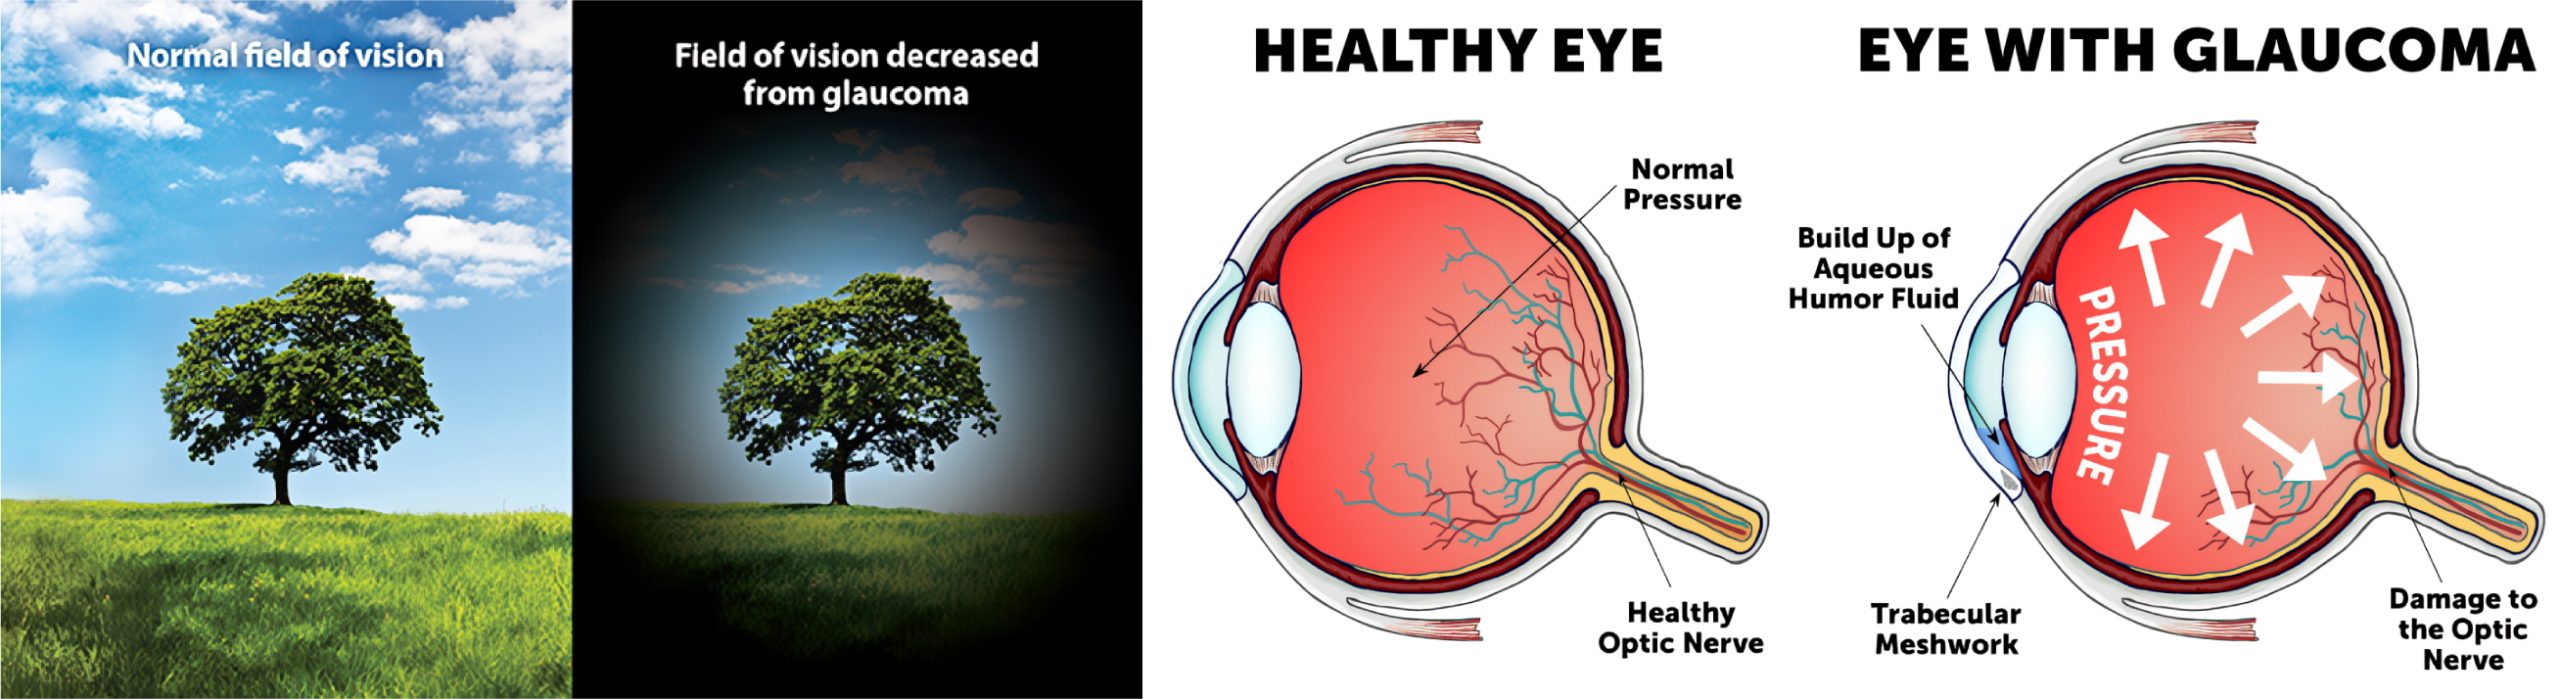

青光眼

青光眼是一类损害视神经的眼疾,视神经在视觉信息传递中扮演关键角色。通常,眼内(IOP)升高是导致视神经损伤的主要原因。这种损伤会引发渐进且不可逆的视力丧失,使青光眼成为主要的致盲眼疾之一,约占所有盲症病例的5.3%至21%。青光眼主要分为开角型和闭角型两种类型。

开角型青光眼是一种多因素引起的视神经病变,其特征是视盘和视野发生变化。中医将此病症对应为“青风内障”,特点是视力逐渐下降,通常在早期无明显症状。中医认为,开角型青光眼的病因病机可能与先天体质不足、命门火衰、脾阳不振、湿痰内生、肝郁气滞、肝肾阴虚等因素相关。这些因素导致目中脉络受阻,神水运行不畅。

闭角型青光眼则由前房角关闭引起,导致眼压急剧升高,引发剧烈眼痛、视力模糊,有时伴有恶心等急性症状。中医认为,闭角型青光眼的病因病机多为邪热内犯、肝胆火热、情绪激动、脾湿生痰等,这些因素导致目中玄府闭塞,神水排出受阻。若不及时治疗,开角型和闭角型青光眼均可导致失明。

中医眼科医生结合中药,辅助西医常规的降眼压手法,以调节患者全身状况,稳定眼压,改善视功能。由于青光眼早期症状不明显,定期眼科检查对于早期发现和调理至关重要。此外,在青光眼的长期调理过程中,除了考虑患者病情、年龄、性格等因素外,还应注意情绪波动、心理变化对眼压的影响,并配合中药进行调理。